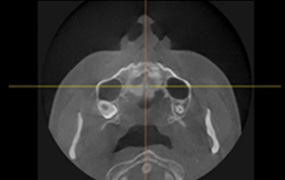

3D-CT

입체분석

을 통한

심층검사

수술 전 3D-CT 입체 분석을 통해

환자의 코 뼈는 물론 코 주변 연부 조직의

모양, 상태, 크기까지 정밀하게 검사하여

환자 개개인에 맞는 1:1 맞춤 수술을 계획합니다.

연골 비대칭 및

비중격 만곡증의 유무

하비갑개 비후 및

코막힘 문제해결

비중격 연골의

상태와 크기 분석

코 뼈의 넓이